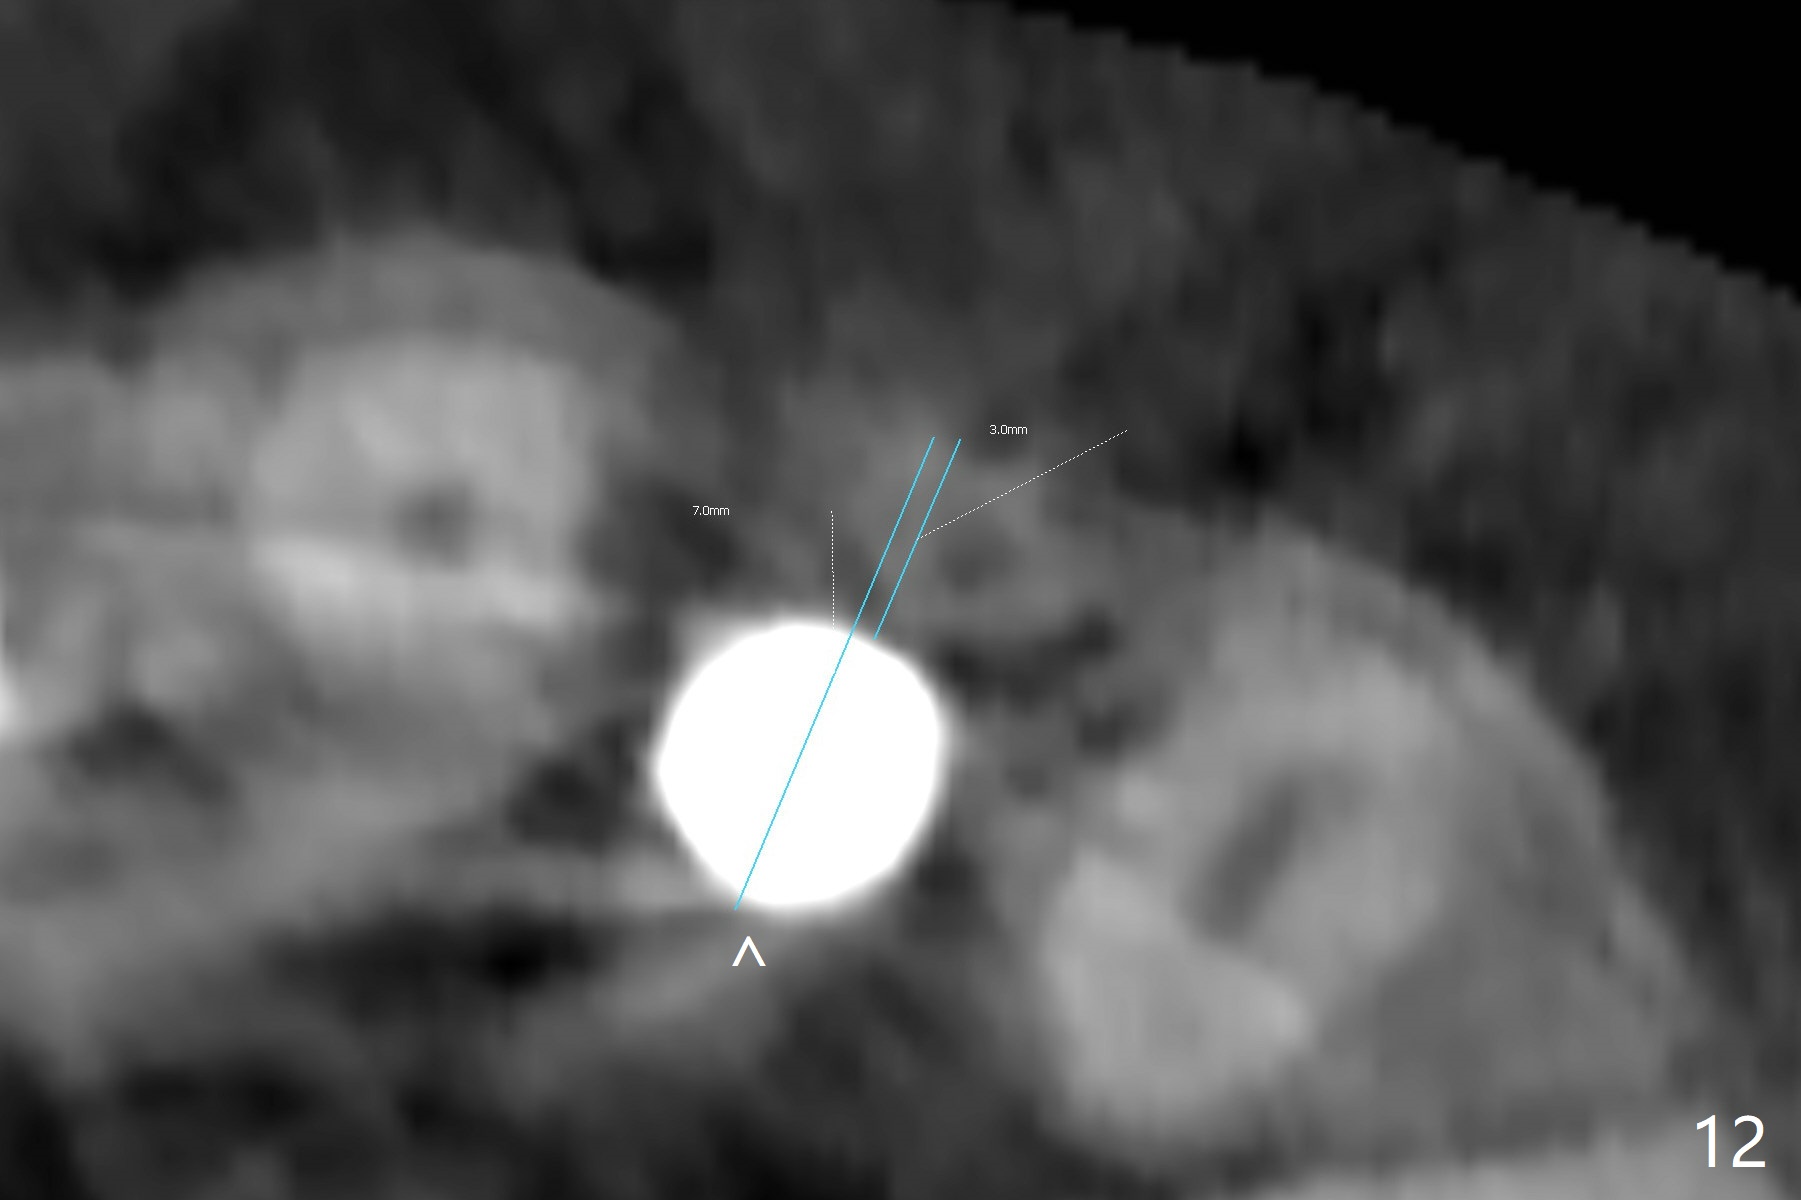

When the patient returns, the crown at #10 has displaced incisally (Fig.1,2 arrow). The initial depth is 15 mm (Fig.3, palatal gingival margin). After a 3.8x12 mm SM implant is placed (Fig.4), allograft is packed in the peri-implant space (*, as compared to Fig.3) and a 3.9x4(3) mm abutment is placed (A). More allograft is placed in the peri-abutment space (Fig.6 *). The existing crown (Fig.4,5 C) is hollowed, relined (R) and used as an immediate provisional (Fig.7-9). The patient is pleased with the appearance of the apically-repositioned provisional (Fig.7 arrow). She returns for impression 3.5 months postop (Fig.10). After change of abutment to 3.9x4(4.5) mm and new provisional, impression is retaken 5 months postop (Fig.11,12). It appears that the implant is palatally placed and a little large for the site (Fig.11 (B: buccal); Fig.12 (^: thin layer of the palatal plate)). If an angled abutment were used, a screw-retained crown might have been feasible. Due to the new provisional, the gingiva looks healthy when a permanent crown is cemented (Fig.13).